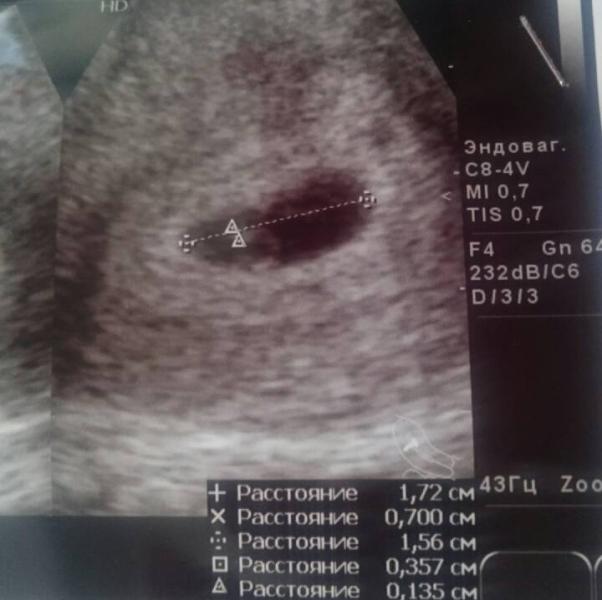

Здравствуйте девочки. Вчера что то разпаниковалась и была в шоке от наших больниц. Болел живот и начались выделения (коричнево- красные, светлые) вызвала скорую. Скорая приехала у меня плюс ещё температура. Увезли в больницу. В больнице начался цирк. Меня посмотрели -в больницу элементарно не было пеленок для кресла, постелили листки а4 использованые! Посмотрели сказали выделения не сильные. Температура 37,4 не температура. Сказали сходить ещё раз на узи и хгч сдать для динамики. Хотя у неё сто...